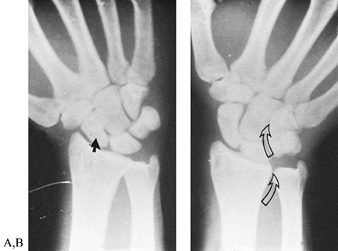

Figure 42.2. Posteroanterior views of a normal wrist in radial and ulnar deviation. A: In radial deviation, the scaphoid is palmar flexed, and its shortened appearance is sometimes misinterpreted as a fracture (closed arrow). B:

The outline of the scaphoid is best visualized with the wrist in ulnar deviation. This wrist position also demonstrates the relationships between the forearm and carpal bones. In ulnar deviation, the radioulnar, lunate-triquetral, and capitate-hamate joints (open arrows) line up to form a sinusoidal curve. |